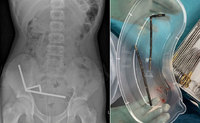

“배 아프고, 소변도 안 나와”… 알고 보니 ‘이것’ 삼킨 게 원인이었다